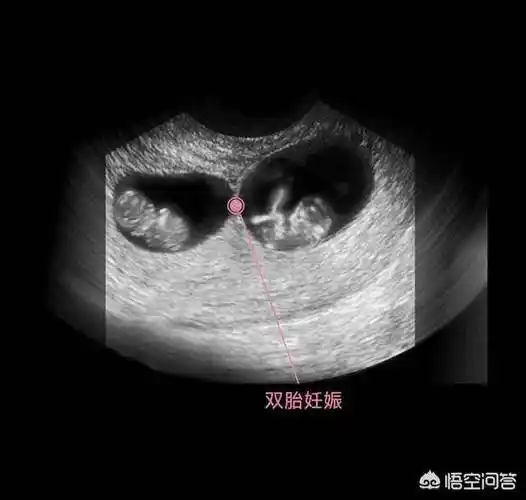

我的双胎宝宝的9周照_双胞胎_孕囊_预产期_母婴_孕产经验

双胞胎,因为它有两个胎囊,需要等胚胎出现胎心和胎芽,也就是要9周左右